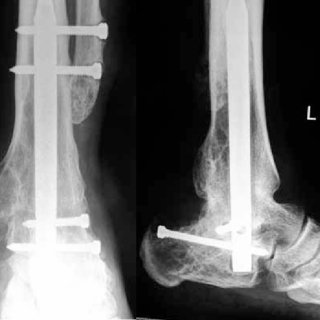

It is common following a fracture or other injury for a change in weight bearing to be prescribed. This is because it has been thought that increasing weight bearing would delay healing.

However a recent paper argued the opposing point of view, that early weight bearing meant was beneficial as you didn’t get the significant detrimental effects, especially in an older population, linked with prolonged immobilisation.